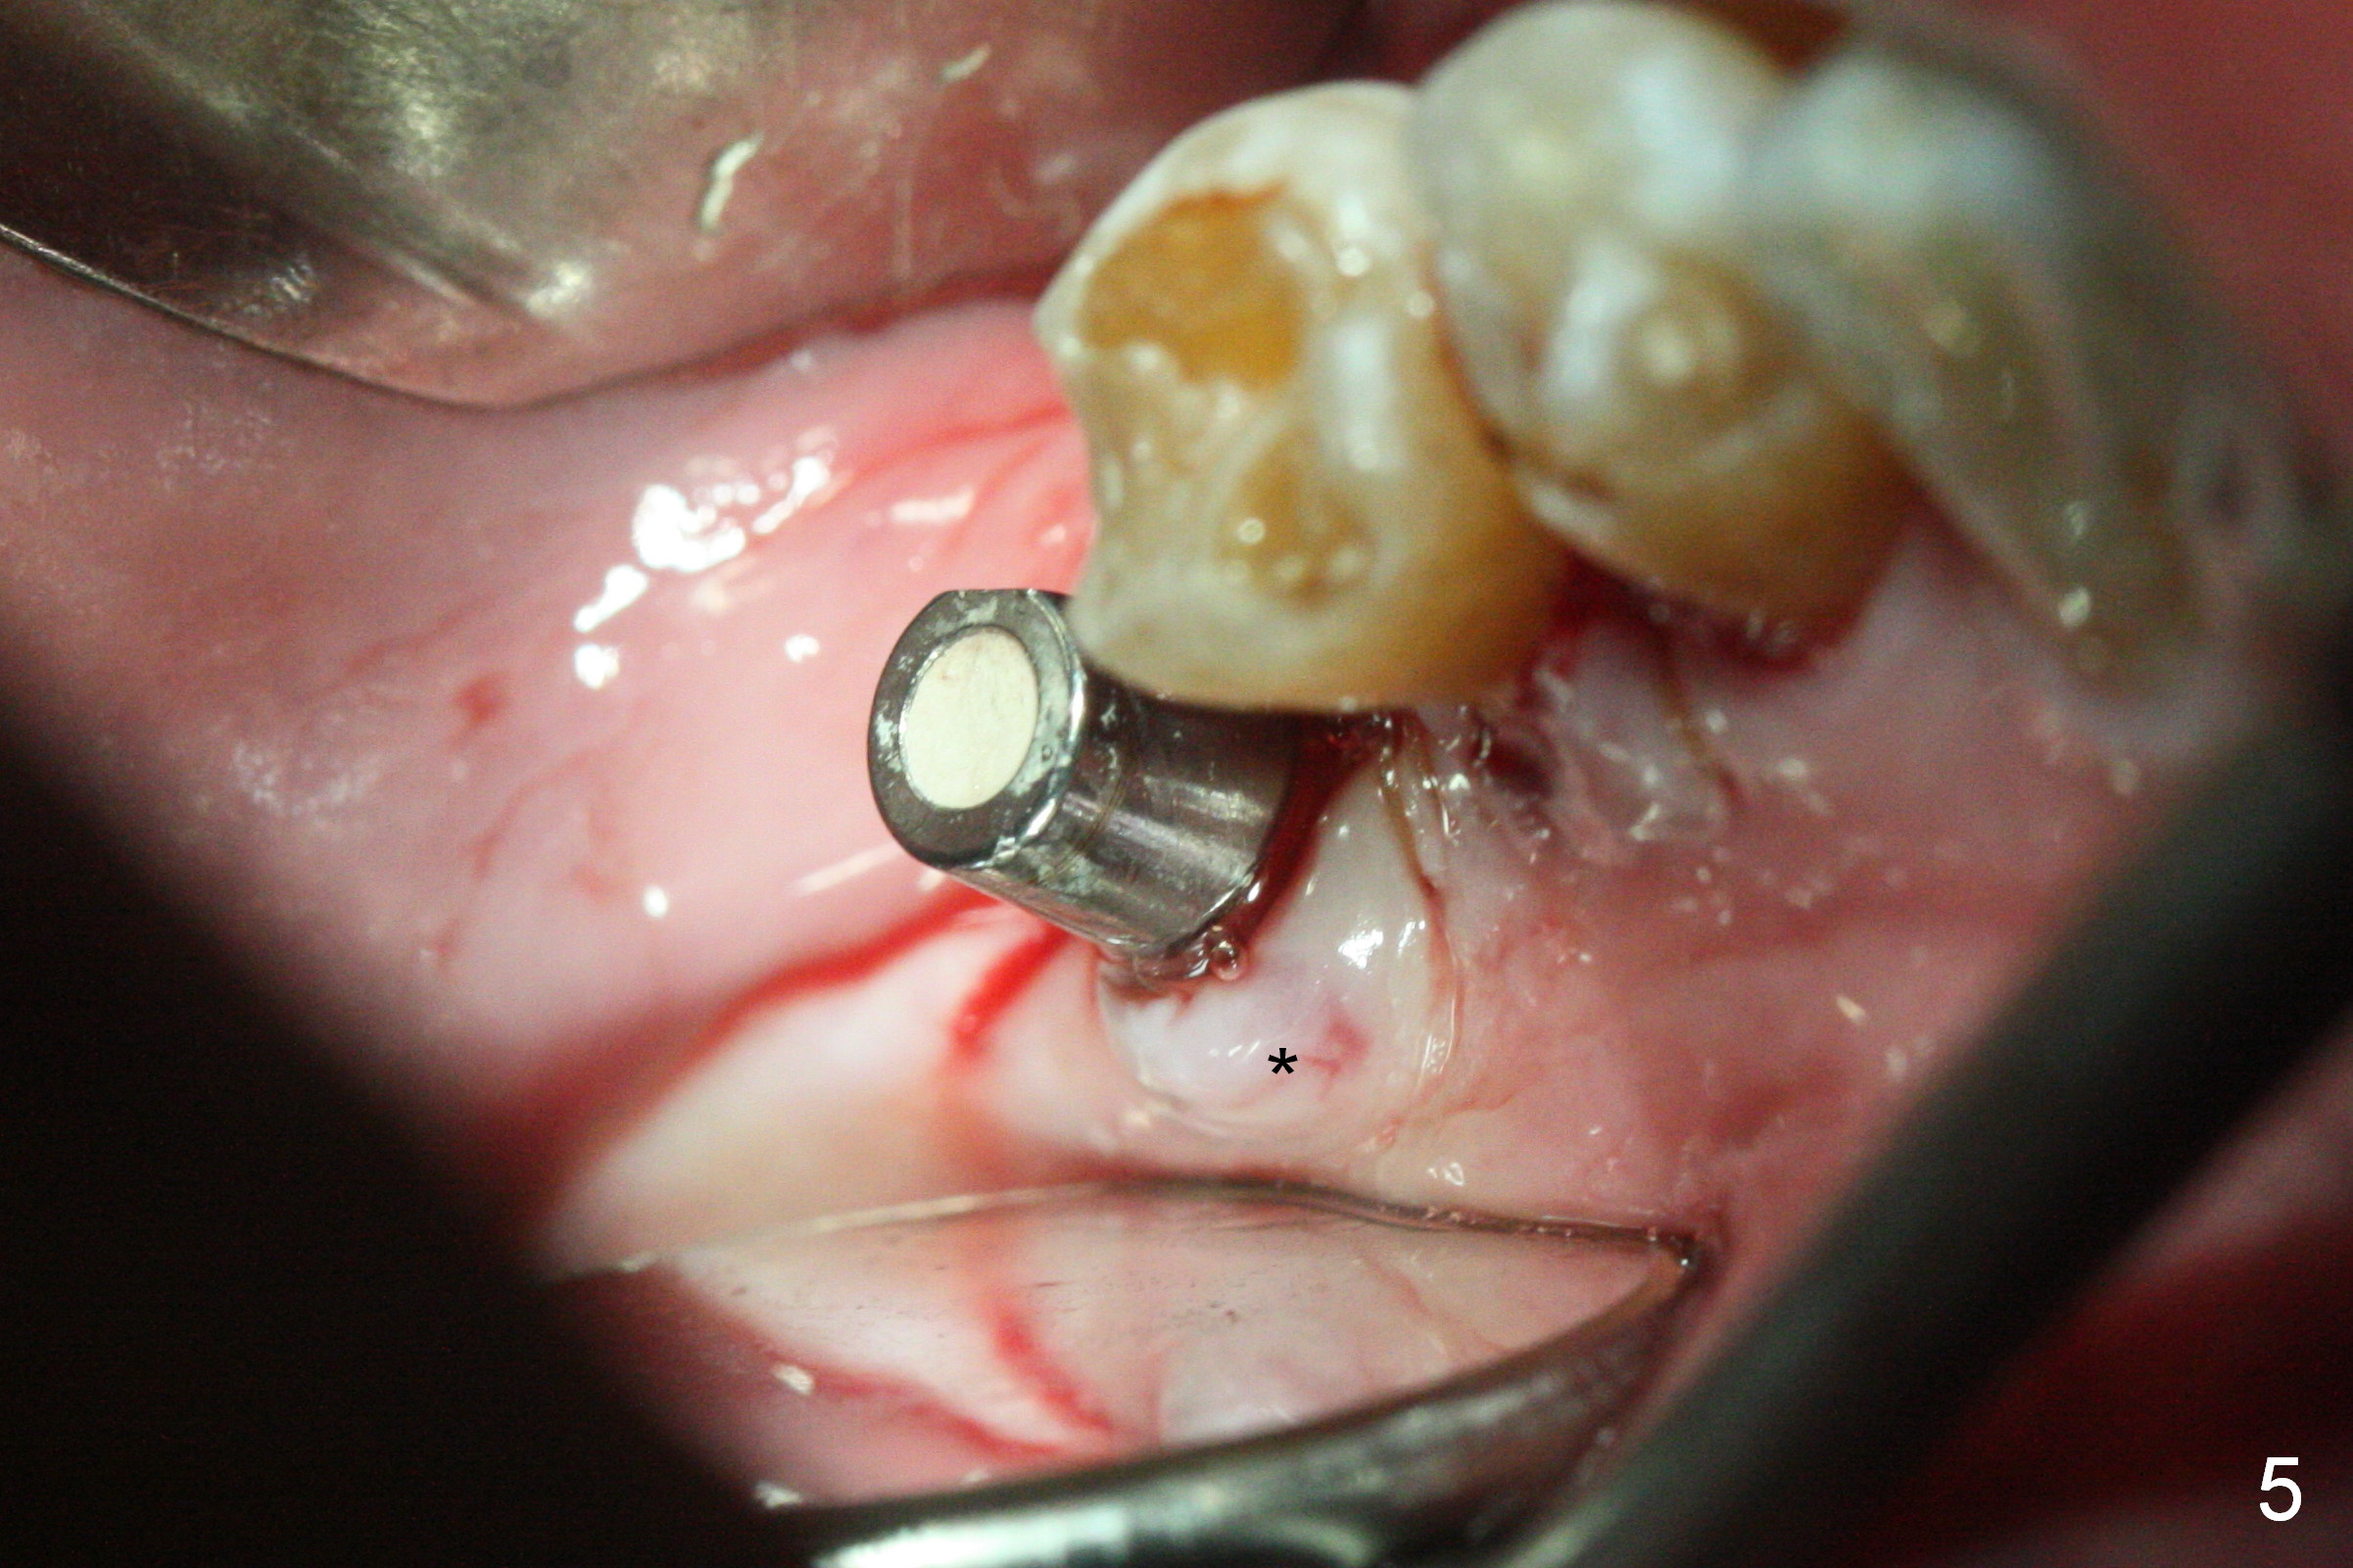

As indicated by CBCT, the ridge at the site of #19 is pointed (Fig.1). After regional ridge reduction (Fig.2) and use of 2 mm pilot drill for 8.5 mm, the depth is actually ~ 10 mm. After sequential osteotomy until 4.3x10 mm drill, the osteotomy is in fact 11.5 mm deep; a 5x11.5 mm implant is placed with <35 Ncm (Fig.3). Panoramic X-ray shows the implant close to the superior border of the Inferior Alveolar Canal (Fig.4 red dashed line). The ridge looks wider and more bulging (*) when a 6.5x5.5(5) mm abutment, allograft/Osteogen and Osteotape (GBR) are placed (Fig.5 (lingual) and 6 (buccal)). Periodontal dressing is then applied. There is no postop paresthesia. The abutment dislodges 3 weeks postop. A healing abutment is placed (6.5x4 mm). The patient returns for restoration 4 months postop; bone density appears to increase around the implant (Fig.7 arrowheads). When a 7.5x5(4) mm abutment is placed, there is transient pressure on the gingiva (blanching). The mesial gingival trough is formed by Diode laser prior to impression.